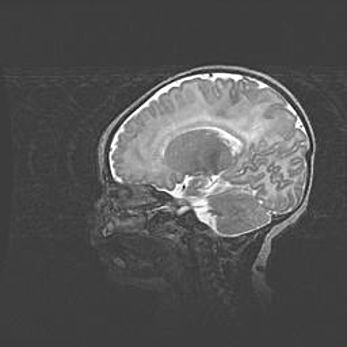

Сообщающаяся гидроцефалия. Кистозная энцефаломаляция головного мозга.

Возраст: 3 месяца 4 дня

Вес: 3100 г

Пол: женский

Окружность головы: 34 см

Срок гестации: 31 неделя

Кистозная энцефаломаляция головного мозга - одна из форм поражения головного мозга в детском возрасте. Характеризуется возникновением множественных и распространённых кист в коре, белом веществе и подкорковых образованиях головного мозга у плодов, новорождённых и детей раннего возраста. Развитие кистозной энцефаломаляции связано с внутриутробной асфиксией и гипотонией, родовой травмой, тромбозом синусов, пороками развития сосудов, инфекциями, сепсисом и другими причинами. Наиболее значимые инфекционные агенты: вирусы простого герпеса, цитомегалии, краснухи, токсоплазмы, энтеробактерии, золотистый стафилококк и другие.